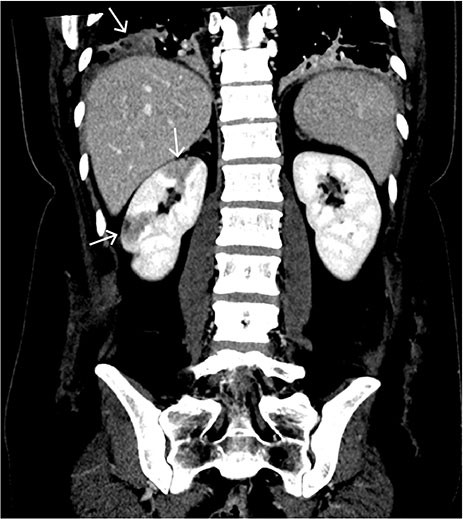

Ut fra arbeidsdiagnosen ble det gjort CT pulmonal angiografi, som viste lungeembolier i høyre hovedarterie samt segmentalt og subsegmentalt i lungearteriene bilateralt (figur 1). Både i høyre og venstre lunge ble det oppdaget basale, perifere, kileformede lungefortetninger som kunne indikere lungeinfarkter. Samtidig ble det påvist en lett utvidelse av truncus pulmonalis på 34 mm, som ytterligere støttet mistanken om forhøyet pulmonaltrykk og høyrebelastning.

CT abdomen med intravenøs kontrast viste skarpt avgrensede, perifere, kileformede, hypodense områder i høyre nyre best forenlig med ferske nyreinfarkt (figur 2). Det ble ikke påvist blødning eller øvrig aktuell patologi i abdomen.

Hypodense lesjoner i nyreparenkymet kan sees ved hypoperfusjon og skyldes oftest akutt nyreinfarkt eller pyelonefritt. Grunnet skarpt avgrensede perifere, kileformede lesjoner og fravær av reaksjon i perirenalt fettvev passet funnene best med et nyreinfarkt. Dette er en sjelden tilstand hvor komplett eller partiell okklusjon i nyrearterien eller dens grener fører til iskemi i nyren. Nyreinfarkt kan manifestere seg med flankesmerter, kvalme, feber og hematuri (3). Det kliniske bildet kan imidlertid være subtilt, og diagnosen kan bli oversett. Tilstanden kan bli komplisert med nedsatt glomerulær filtrasjon og nyresvikt.